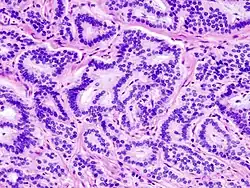

Neuroendokrine Tumoren

Serotonin spielt häufig bei neuroendokrinen Tumoren, das heißt bei gut- oder bösartigen Tumoren mit Eigenschaften von Nervenzellen (Neurone) und hormonproduzierenden (endokrinen) Drüsen, eine zentrale Rolle. Das Karzinoid, eine Sammelbezeichnung für neuroendokrine Tumoren, meist des Magen-Darm-Trakts, aber auch z. B. des Bronchialsystems, ist durch die Überproduktion von Gewebshormonen, insbesondere Serotonin, geprägt. Im Gegensatz zu den meisten anderen Tumoren sind die charakteristischen Symptome des Karzinoids nicht auf eine Verdrängung von gesundem Gewebe, sondern insbesondere auf die Wirkungen des erhöhten Serotoninspiegels zurückzuführen. Ein erster Hinweis auf eine karzinoidbedingte Erhöhung des Serotoninspiegels im Magen-Darm-Trakt sind anhaltende Durchfälle und Bauchkrämpfe. Bei einer erhöhten Serotonin-Produktion außerhalb des Magen-Darm-Trakts, beispielsweise nach Metastasierung, sind systemische Serotonin-Wirkungen, wie das Flush-Syndrom, zu beobachten.[28] Ist der Serotoninspiegel karzinoidbedingt über eine längere Zeit erhöht, treten als Folge der hypertrophischen Wirkung des Serotonins Fibrosen, insbesondere der Trikuspidalklappen und Pulmonalklappen des Herzes, auf.[75]